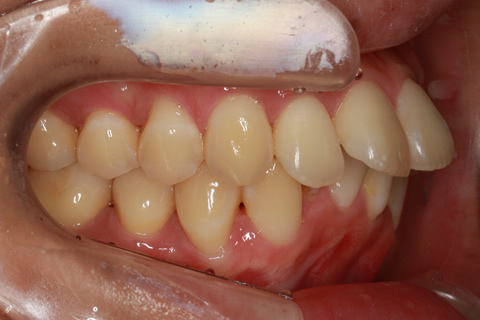

矯正期間6ヶ月

前歯のみの部分的舌側矯正4

治療前

治療中

治療後

- 年齢・性別

- 28歳女性

- 治療期間

- 6ヶ月

- 抜歯

- なし

- 治療費

- 50万円

- 備考

- マルチブラケットを用いた矯正治療

- 治療内容

- 非抜歯にてIPRを併用したリンガル矯正治療。

- 施術の副作用(リスク)

- 表側矯正と比較して、前歯のラビッティング(舌側傾斜)を起こしやすい。